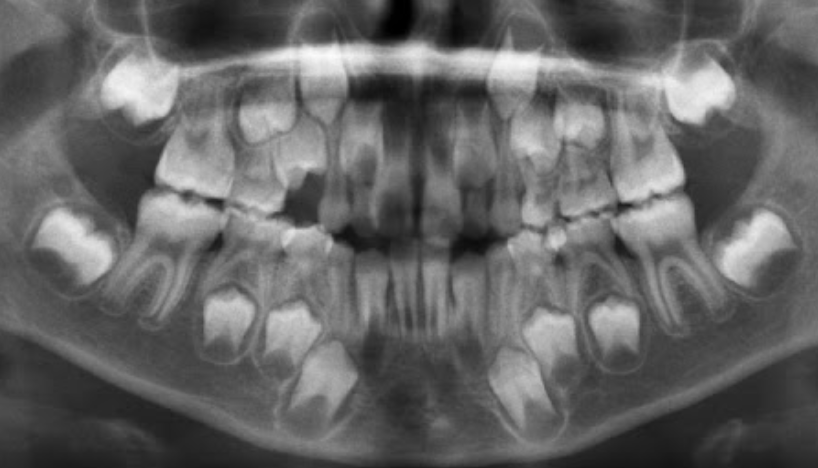

1.Ad. LOWER central incisors present? Yes. definitely 6-7 or older

1. Ad. UPPER CI present? Yes def. 7-8 y.o

3.Ad. Upper LAT incisor present (baby sheds 7-8)? NO so still under 7-8

Conc: pt is under 7